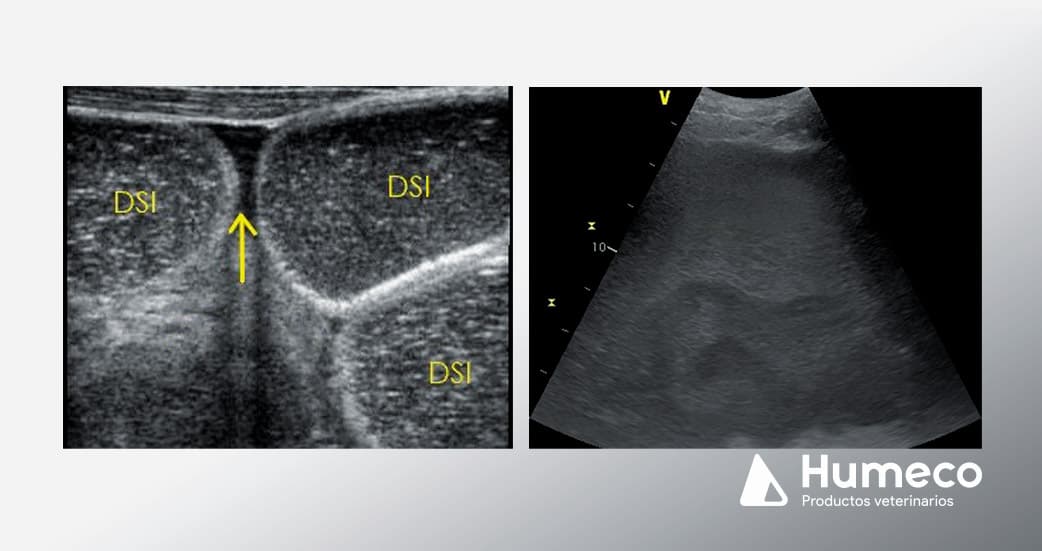

Colocar la sonda a la altura del esternón en la línea media ventral y desplácese hacia abajo. Las asas normales del intestino delgado están colapsadas o ligeramente distendidas y suelen identificarse en la profundidad del bazo y en la región inguinal. El colon grueso se localiza en la parte ventral del abdomen. Las lesiones de estrangulamiento del intestino delgado se asocian a asas de intestino delgado distendidas (DSI) y amótiles, que suelen identificarse en el abdomen caudoventral (imagen 1). Las asas normales del intestino delgado suelen visualizarse como múltiples densidades redondas y móviles, sin distensión.

Evaluación del líquido peritoneal